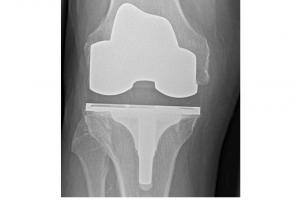

Actualité publiée il y a 7 années 2 moisARTHROPLASTIE de la HANCHE et du GENOU : Un taux de réussite élevé, un résultat durable